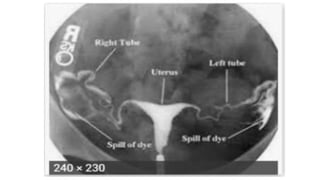

HYSTEROSALPHYNGOGRAPHY(HSG)

• Hystero+salpingo+graphy

• Hystero- uterus

• salpingo- fallopian tubes

• Graphy – radiolological procedure

• Assessment of tubal patency

• Detection of uterine malformation

• Diagnosis of cervical incompetence

• Detection of translocated IUD

• Radio-opaque dye 5-10ml

• Radiographic x rays

• TIMING OF PROCEDURE

• HSG is done D6 and D 10 of cycle

• Antiobiotics given one day before procedure upto 5 days